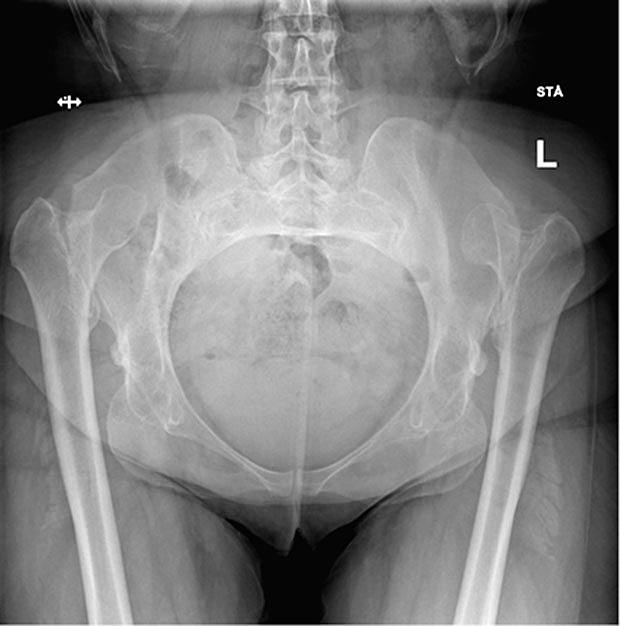

Røntgenundersøgelsen af bækkenet viste, at begge hofteled var bilateralt lukserede ca. 10 cm kranialt med hypoplastiske capiti femoris og knap udviklede, meget stejlt forløbende acetabuli. Der syntes ikke at være udviklet neoacetabuli.

En 35-årig kvinde, som kom til Danmark som flygtning, blev i forbindelse med udredning for lænderygsmerter henvist til røntgenundersøgelse af bækken og hofter. Hun havde en længere anamnese med smerter i ryg og diffus udstråling til begge ben. Under sine fire graviditeter havde hun haft bækkenløsningssymptomer. Hun angav, at hun var født med hoftedysplasi, men at hun ikke var blevet nærmere undersøgt eller havde fået behandling herfor. Ved en objektiv undersøgelse fandt man øget lændelordose med anteriort kippet bækken, nedsat abduktion i hofteleddene og bilateral positiv Trendelenburgs test. Sensibiliteten var diffust nedsat uden radikulært præg, og hun havde en nedsat gangdistance pga. smerter.